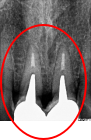

「右下の1番後ろの歯が浮いたような感じで、グラグラしていて噛むと痛みもあります。」とのこと。レントゲンで詳しく調べると、噛み合わせの問題と歯周病の進行が原因で、奥歯の周りの骨がなくなってしまっていました。この歯は残念ながら抜歯になることをYさんにお話しし、他の歯が多く残っているので、インプラント治療をおすすめしました。(インプラントは他の歯に負担をかけないので、残っている歯を守ることができます。)

Before

冠の中で大きな虫歯になり支台の役割を果たしていませんでした。

【インプラント埋入前】

冠はブリッジを切断しただけで取れてきました。軟化象牙質を取り除いたところ、歯根しか残っていない状況で保存できるかどうかのぎりぎりのところでした。